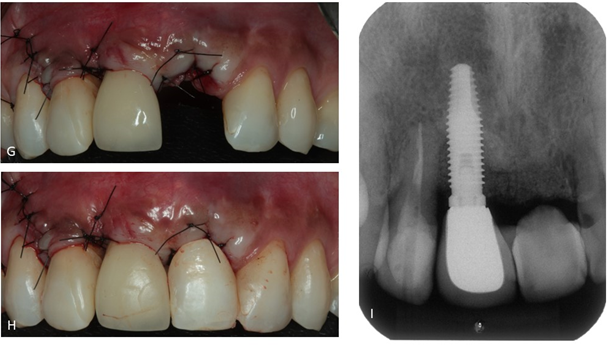

Após reavaliação da terapia básica, constatou-se necessidade de terapia cirúrgica envolvendo a extração do dente 21 e confecção de provisório, descontaminação do defeito e preenchimento com biomaterial.

Também foi proposto o tracionamento do elemento 12 com o uso de aparelho ortodôntico para posterior exodontia, a fim de trazer coronalmente todo o conjunto periodontal. O tracionamento ortodôntico— incluindo dente, osso e tecidos moles — é uma técnica eficaz para preservação óssea em dentes com indicação futura de exodontia (Passanezi et al.2019). Assim, o tracionamento coronal é uma alternativa conservadora e previsível para otimizar a futura arquitetura peri-implantar.

Após reavaliação, foi planejada a explantação do elemento 11 e exodontia do 12 e, após seis meses, planejado colocação de implante Cônico HI Implacil Osstem de 3,5x11mm e reabilitação. A paciente não aceitou passar por cirurgia para aumento da espessura e altura de tecido queratinizado, o que poderia melhorar a estética e favorecer a higienização. No entanto, a autonomia do paciente deve ser respeitada e as limitações devem ser explicadas. Nestes casos, o acompanhamento clínico personalizado e manutenções devem ser feitas regularmente para saúde e longevidade do sucesso da terapia de implantes.